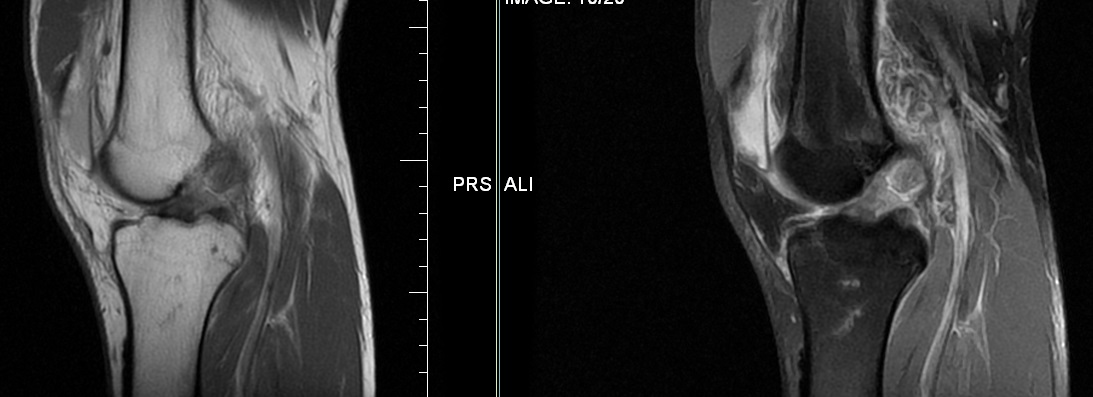

Upload Date: January 23, 2019 Full Size Image Dimensions: 1093 × 397 Image Parent Post: Ρήξη Προσθίου Χιαστού Συνδέσμου (ΠΧΣ)

3.Μαγνητική εικόνα ρήξης ΠΧΣ